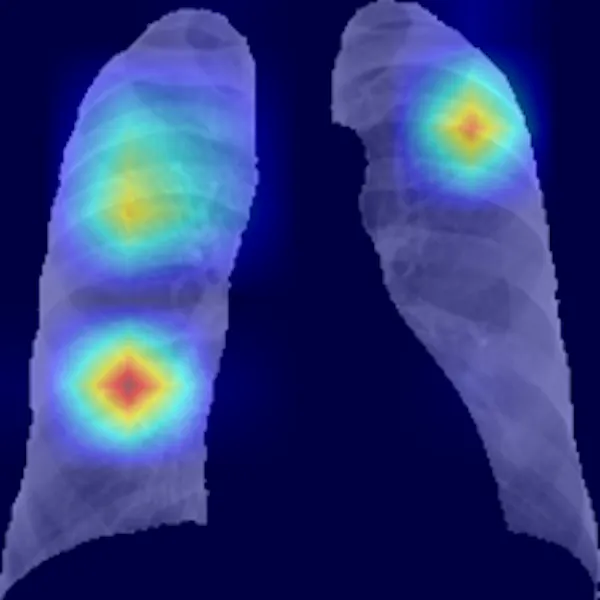

Apoyados en la capacidad que los modelos basados en inteligencia artificial tienen para obtener información que incluso está oculta al ojo humano, investigadores de la Universidad de Antioquia, la Johns Hopkins University y la Universidad Politécnica de Madrid hemos desarrollado un prototipo de sistema computarizado de diagnóstico de la covid-19 y de evaluación del grado de afectación de los pulmones a partir de imágenes radiológicas de tórax. Dicho sistema ha sido desplegado en un prototipo de aplicación en la nube siguiendo un modelo de software como servicio.

La herramienta proporciona un método objetivo complementario, mínimamente invasivo para el diagnóstico, que evalúa el grado de afectación por la covid-19. Alcanza una precisión por encima del 90%, superior incluso a la alcanzada por los expertos en radiología. Además, proporciona evidencias con capacidad diagnóstica en estadios incipientes de la enfermedad (los cinco primeros días).

La herramienta también identifica el área de mayor afectación y permite cuantificar de forma objetiva lo extenso de la infección. Sin olvidar que reduce significativamente el tiempo dedicado por los expertos en radiología a la evaluación de cada paciente.